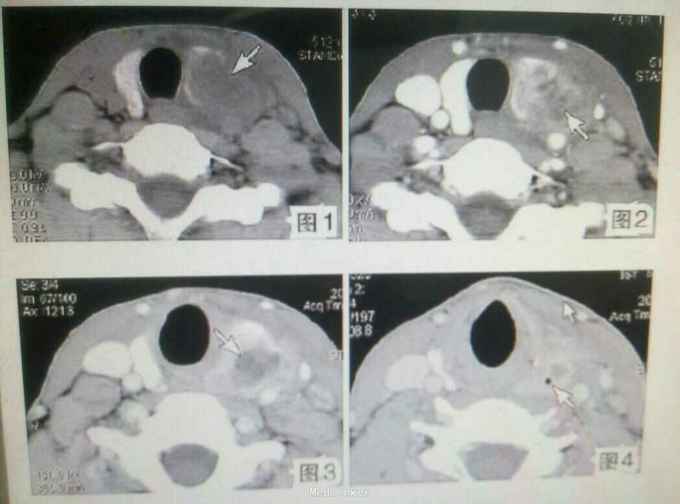

查体:气管右移,颈前区偏左可触及一约3.1cm×2.0cm大小肿物,质韧,表面光滑,边界清楚,活动度好,有压痛,有囊性感,可随吞咽上下活动。 辅查:超声检查:甲状腺左叶内低回声结节,周界清,内少许无回声区,诊断甲状腺腺瘤囊性变。 影像学诊断:甲状腺脓肿

随访与讨论:患者经手术及抗炎治疗后患者恢复良好,痊愈出院。 甲状腺脓肿少见,临床多有局部皮肤红肿疼痛,有压痛,可提示诊断;临床表现不典型时诊断困难;影像学检查发现病变内气体是正确诊断的主要依据,薄层高空间分辨率CT影像显示微小气泡的敏感度高、特异性好,是诊断甲状腺脓肿的重要方法。甲状腺脓肿常由化脓性细菌引起,临床表现为甲状腺局部红、肿、热、痛,常伴有全身中毒症状。 实验室检查见血白细胞数增高,临床根据其典型症状及体征即可做出诊断。CT是诊断甲状腺疾病十分有效的检查方法。 治疗:1.脓肿穿刺;通过穿刺把脓液抽出,消炎抗菌治疗。 2.手术治疗,主要也是对脓肿病灶进行脓液清除,设置引流,对症抗菌消炎。